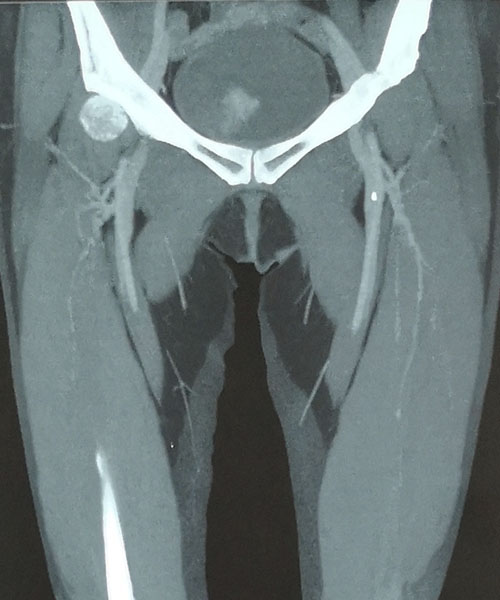

術前CTV評估股靜脈及分支